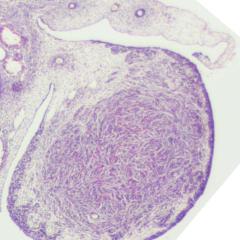

Oocyte

Oocyte Zygote

Zygote Whole Embryo